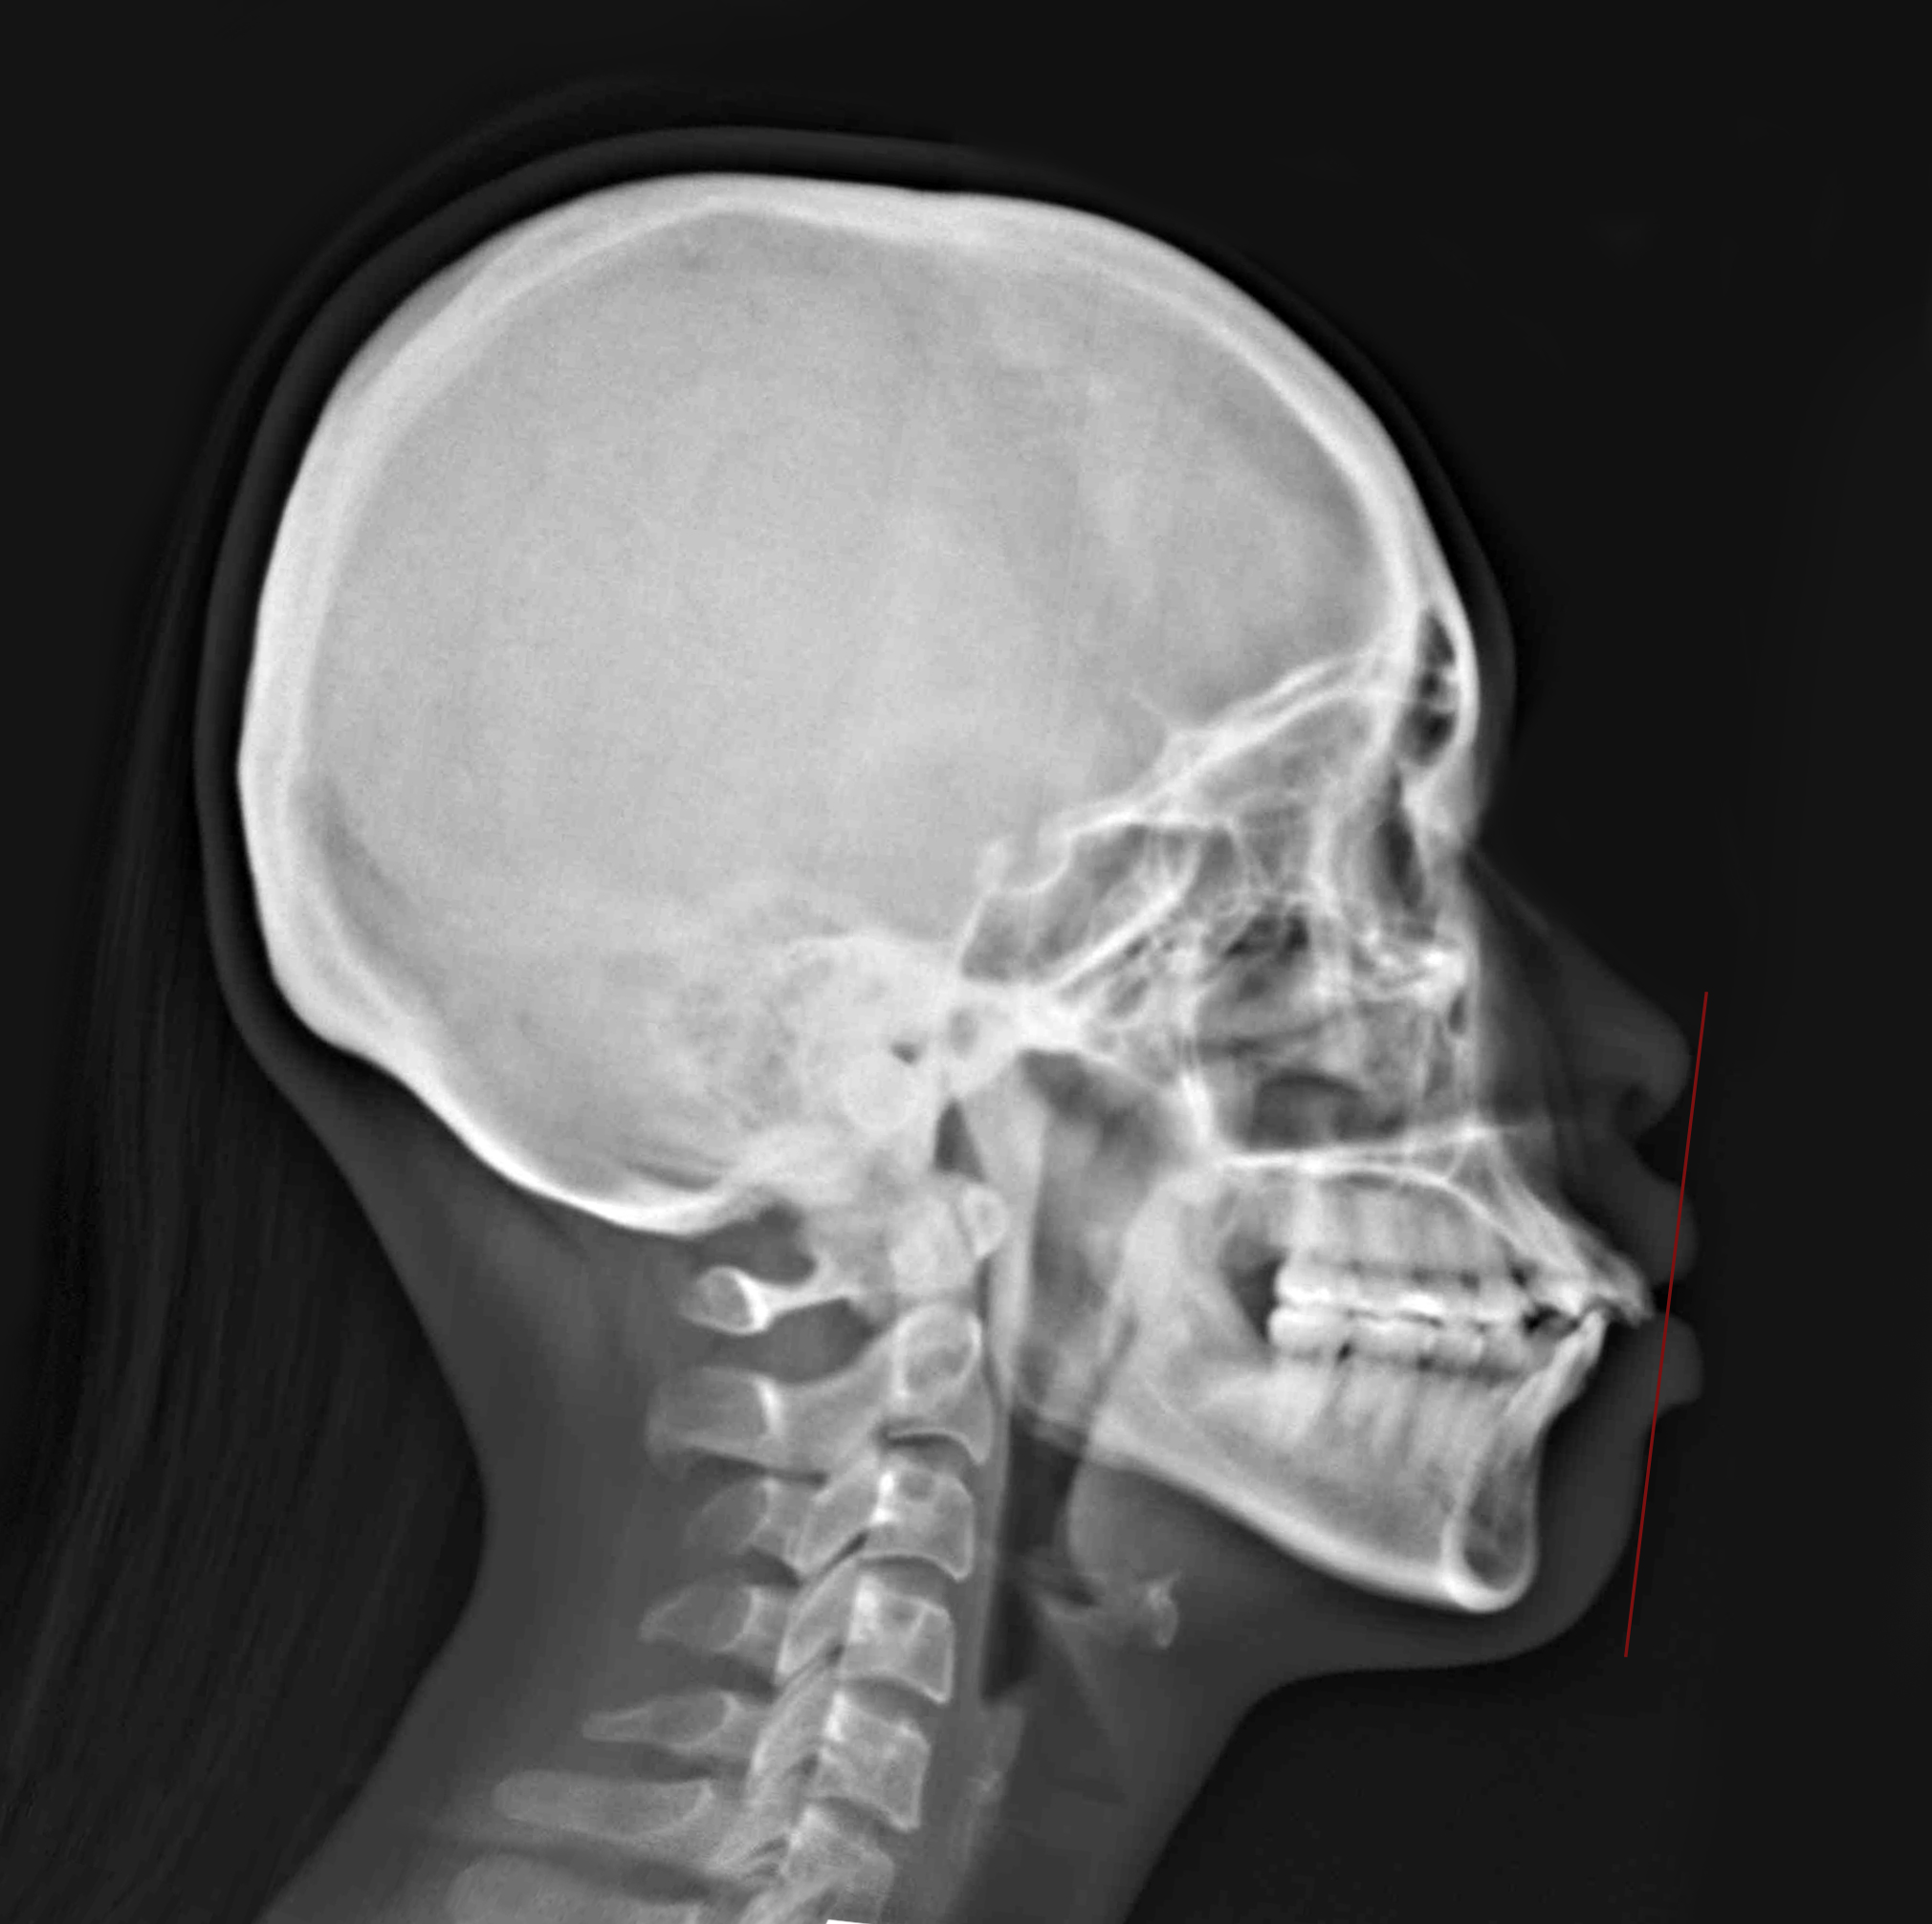

隱適美拔牙改臉型 (一) 首頁 案例分享 齒顎矯正 隱適美拔牙改臉型 (一) 拔牙改臉型 當初客戶最想改善的暴牙...... 經過拔牙四顆小臼齒,與醫師完美的合作,最終也改善了臉型與暴牙,笑起來也更有自信~ 聲明:本所療程皆由專業醫生評估後,依照個人口腔狀況進行治療。因每位患者個別狀況不同,術後狀況也不盡相同,需親來本所由醫生評估。